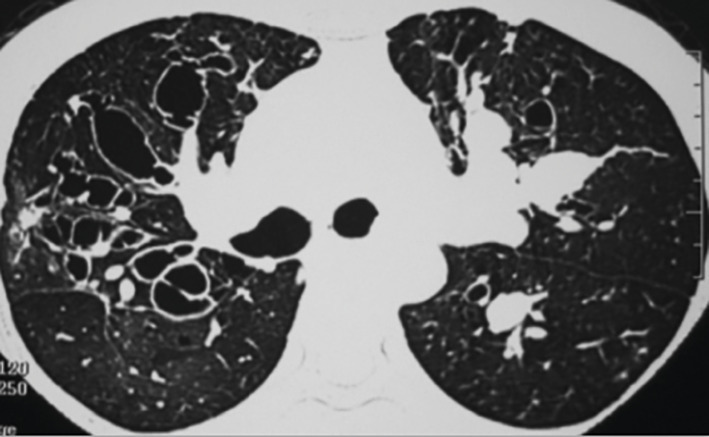

L’ABPA est dite ABPA-S pour sérologique si le scanner est normal, ABPA-B si dilatations bronchiques avec ou sans impactions mucoïdes, ABPA-HAM en présence d’impactions mucoïdes hyper­denses, facteur de mauvais pronostic et d’échec du traitement, et ABPA-CPF devant des signes de fibrose (fig. 1).

L’aspergillome simple (AS ; fig. 2) a l’aspect d’une balle fongique constituée d’hyphes siégeant dans une cavité pulmonaire ou pleurale préexistante ou, plus rarement, dans un foyer de dilatation bronchique. À la radio, c’est initialement un simple épaississement de la surface interne d’une cavité à paroi fine, habituellement au niveau des lobes supérieurs. Aspect typique : image arrondie intracavitaire déclive entourée d’un croissant gazeux.4 L’AS touche des patients immunocompétents. Les manifestations pulmonaires sont rares et discrètes, elles sont liées à l’érosion de la paroi de la cavité par la balle qui peut provoquer une hémoptysie massive.

Contrairement à l’AS, dont la prise en charge est avant tout chirurgicale, l’APC (fig. 3) requiert généralement un antifongique systémique prolongé au moins 6 mois,4 avec parfois un geste chirurgical. Un antifongique à long terme expose aux risques d’interactions médicamenteuses, d’événements indésirables et de résistance.